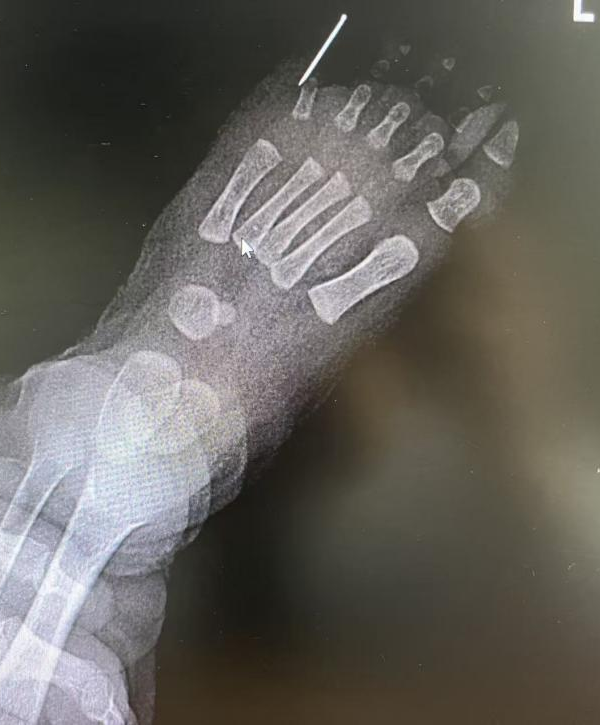

经过细致的体格检查和 X线检查,医生明确诊断患儿为双手、双足均多指(趾)畸形。影像结果显示,左足多出的第 6趾内部存在骨性结构,与正常的跖骨相关联,这增加了手术的复杂性,并非简单的软组织切除。

面对这样幼小的患者和涉及四个肢体的手术,手足外科团队深感责任重大。他们深知,手术不仅要切除赘生指(趾),更要兼顾术后手足的功能与美观,这关乎孩子一生的生活质量。经过周密讨论,团队为宝宝量身定制了精准的手术方案:多指、多趾切除术 +左足第五跖趾关节成形术。

术前 X 线检查